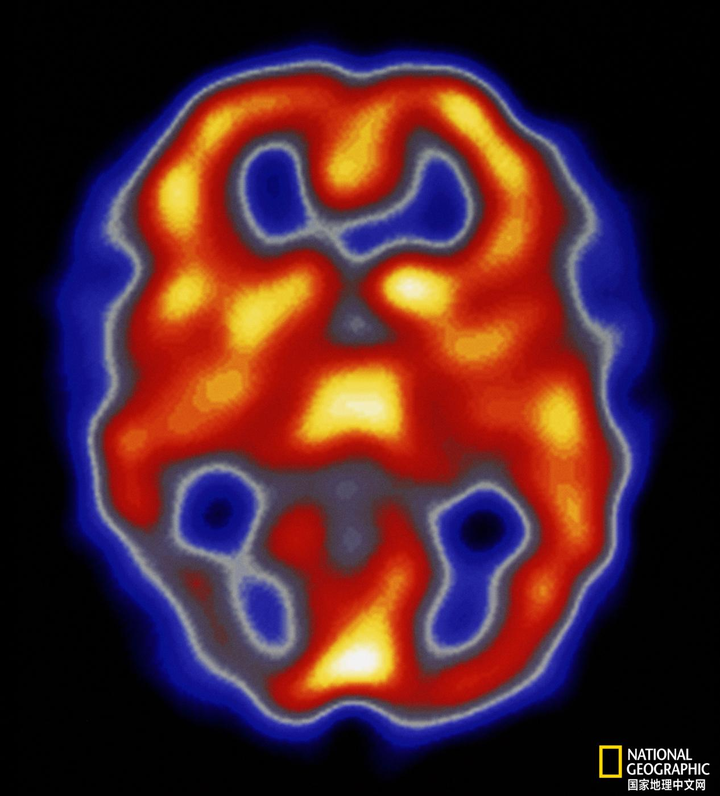

偏头痛发病机制尚未完全清楚,《中国偏头痛诊治指南(2022 版)》将偏头痛定义为“一种常见的神经系统疾病,其临床特征为反复发作性的、多为单侧的中重度搏动性头痛,常同时伴恶心、呕吐、畏光、畏声等症状”。

偏头痛是临床常见类型的头痛,主要是因为血管收缩舒张功能紊乱所引起的颞区疼痛。患者表现为单侧或双侧的搏动性头痛,可以伴有恶心、呕吐、畏光、畏声等临床表现。

由于这种疾病的复杂性,不仅限于其多因素起源,而且还涉及显着的先兆症状,因此人们认为偏头痛是大脑兴奋性改变状态的表现,能够激活遗传易感人群的三叉血管系统个人。